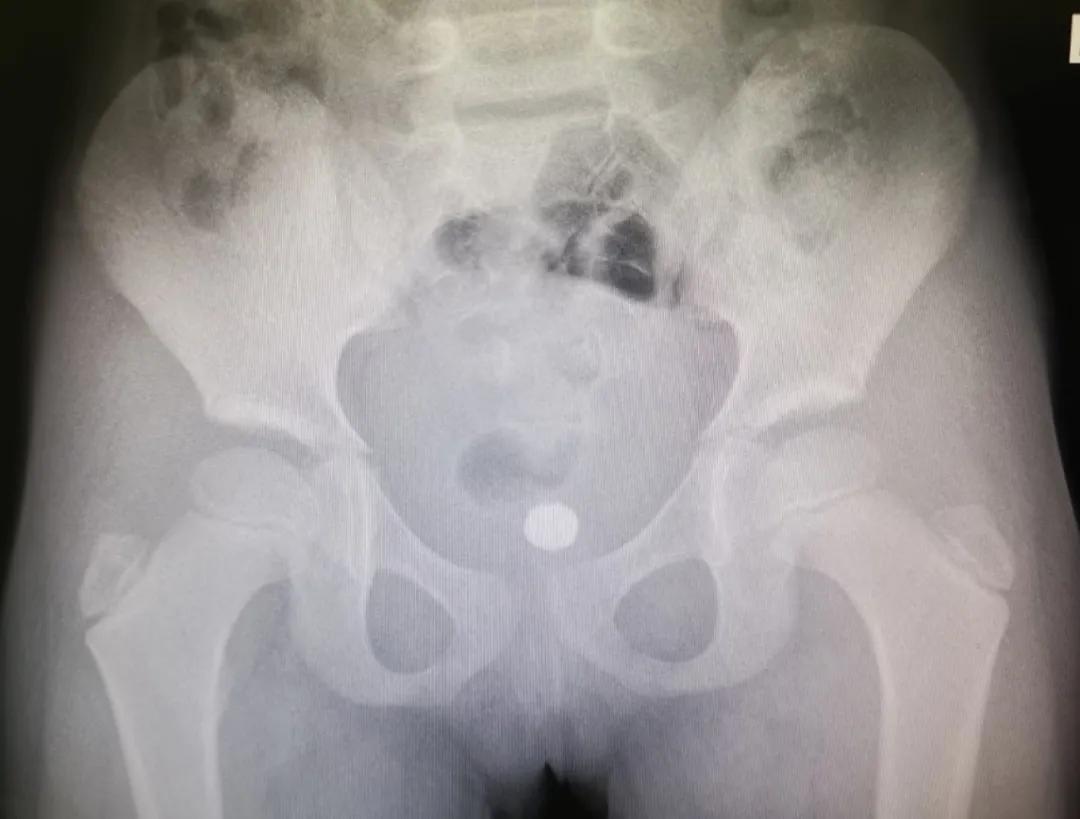

暑假才刚刚开始,南京市儿童医院急诊接诊了一名往丁丁里塞玻璃弹珠的“熊孩子”。

据悉,孩子今年四岁,事发当日下午穿着开裆裤在家中玩耍,因好奇将1枚2-3cm玻璃弹珠小丁丁塞入包皮。孩子当时觉得好玩,接着又塞了1颗。

不长,包皮开始出现红肿疼痛,但仍能自主排尿。此时,家长也终于发现了异常,孩子的小丁丁有明显的两块凸起。经过再三询问,又查看了周围的环境和玩具,才知道孩子把两个玻璃珠塞进去了。

患儿晚上七点多被送至南京市儿童医院,泌尿外科汪俊主治医师立即安排了急诊手术。“幸好玻璃珠并没有进入尿道和膀胱,只是被塞进了*头龟**和包皮之间,包皮水肿造成异物嵌顿,只需将水肿的包皮切开,就可以取出珠子。”

在和家属的充分沟通后,同时行包皮环切术。手术非常成功,两颗玻璃珠被顺利取出,术后也没有感染和肿胀。